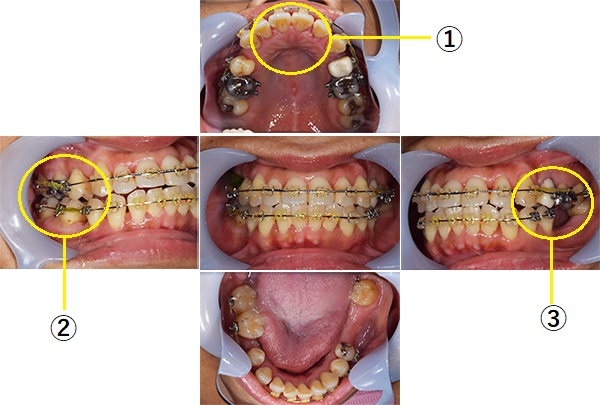

矯正中

【担当医師所見】

左右上下合わせて4本の抜歯を行った

①前歯もキレイに並んできました

②上の歯が外側になり、交叉咬合がなくなりました

③左上の出ていた歯を元の位置までもどしています